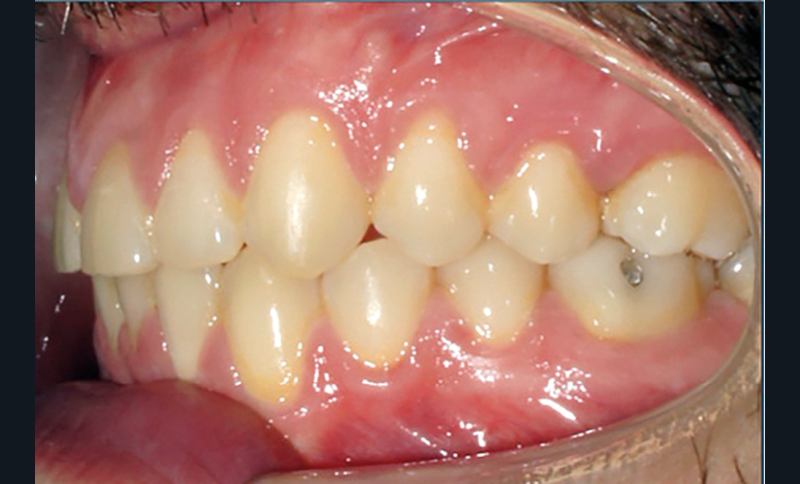

Examen endobuccal (fig. 2a-e)

L’arcade maxillaire est asymétrique, en hémi-lyre droite. Elle présente une mésio-position du secteur 1 en lien avec un encombrement antérieur estimé à 4 mm, se traduisant par une palato-position de la 12 et une rotation de la 11. On observe également des mésio-rotations des premières molaires et une palato-version incisive. L’arcade mandibulaire est ellipsoïde et présente un léger encombrement incisif (1 mm).

Concernant les relations occlusales, on observe une classe II complète subdivision droite. Le surplomb est absent et le recouvrement augmenté, estimé à 4 mm, a provoqué une usure des bords libres de 11 et 21 par attrition. Dans la dimension transversale, on constate une endoalvéolie maxillaire, ainsi qu’une concordance des médianes incisives entre elles, mais toutes deux déviées à droite par rapport au plan sagittal médian.